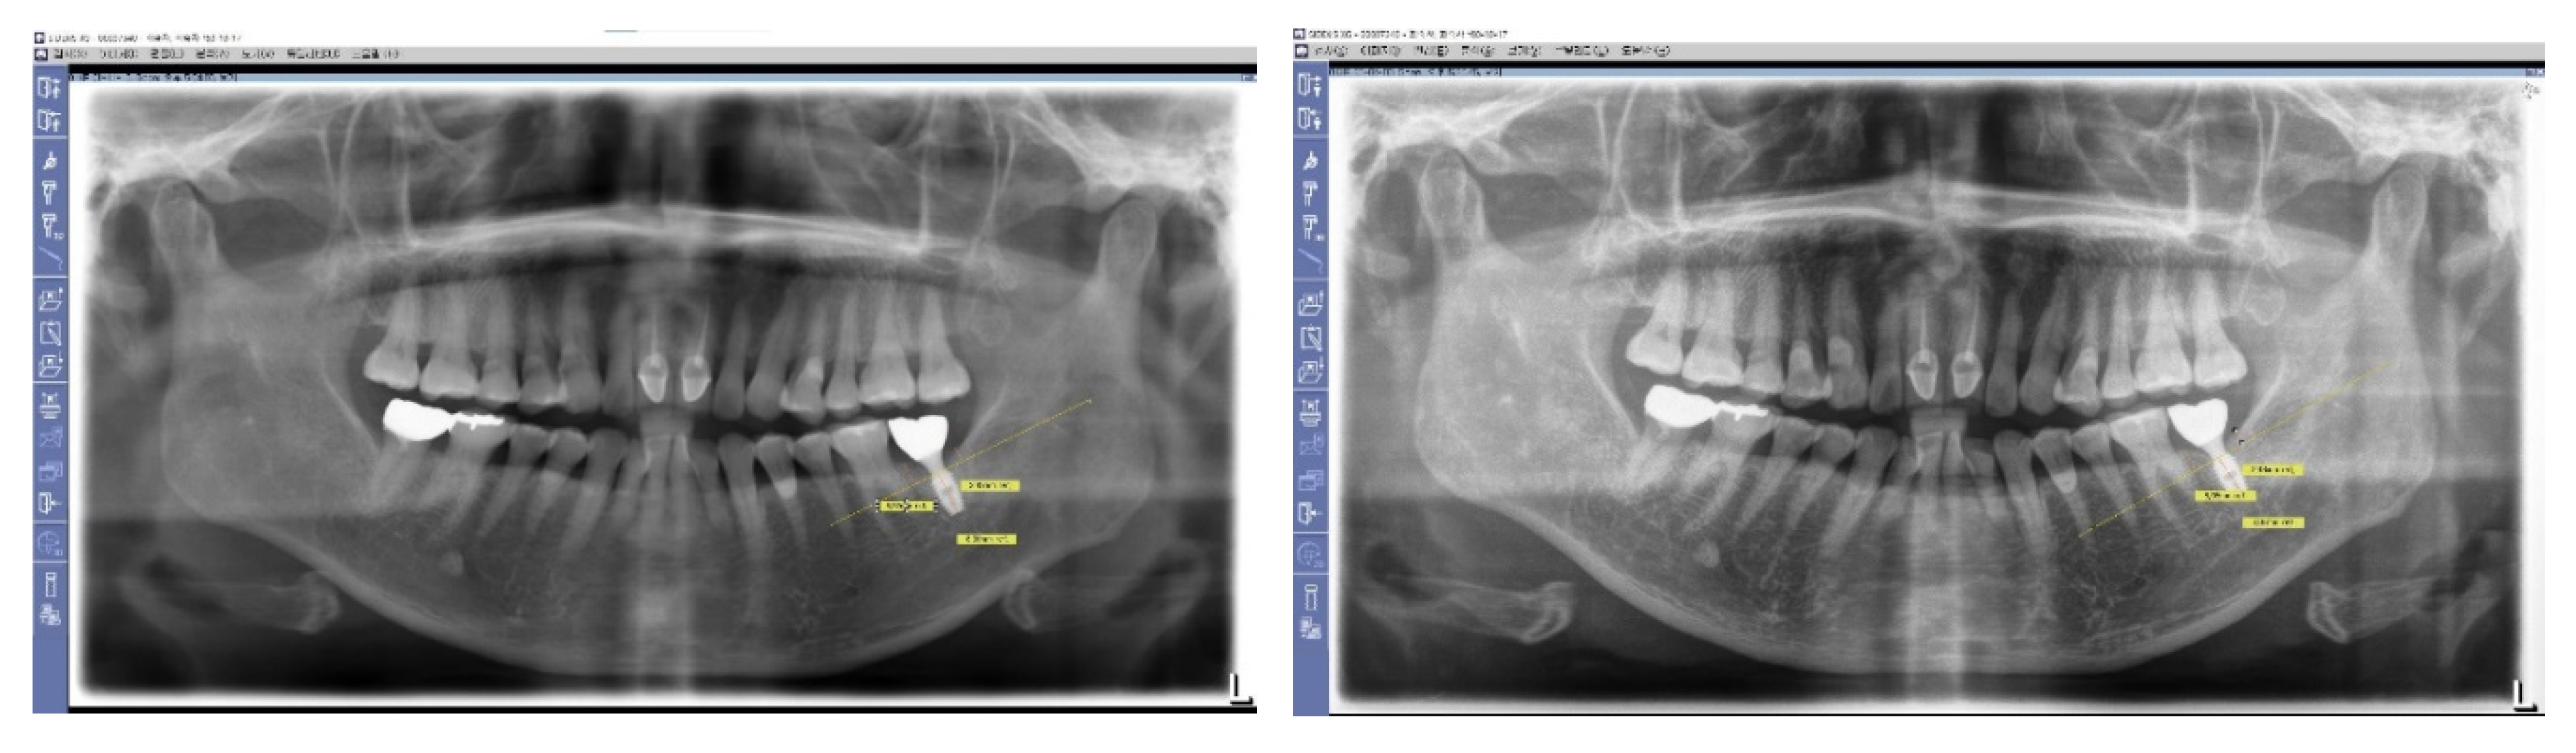

Figure 7. Long-Term Stability of Lower First Implants. This figure displays a panoramic view X-ray taken in 2023, showing the stable results of both lower first implants that were placed in 2012. These implants, which utilize Subcrestally Placed Implants (SPI) with Internal Platform Switching (IPS) design (specifically Bicon implants), demonstrate long-term stability and successful integration.

Figure 9. X-Ray Sequence of Healing Abutment Changes. This series of X-rays illustrates the procedural sequences for implant placement and subsequent adjustments. Initially, healing abutments measuring 5 mm in diameter and 2.5 mm in height were placed and covered with primary flap closure. After three months, a second operation was undertaken for the prosthetic procedure. During this stage, the sites were uncovered and longer healing abutments, maintaining the same profile as the initially embedded abutments, were connected to prepare for final prosthesis installation.